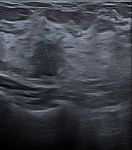

• Ce premier bilan pourra être complété par d'autres clichés ou par une échographie pour être plus précis sur certains diagnostics.

Agée de moins de 40 ans, la mammographie n'est parfois pas nécessaire et peut être avantageusement remplacée par une échographie des seins. C'est le médecin radiologue qui prendra la décision en fonction de votre cas personnel.